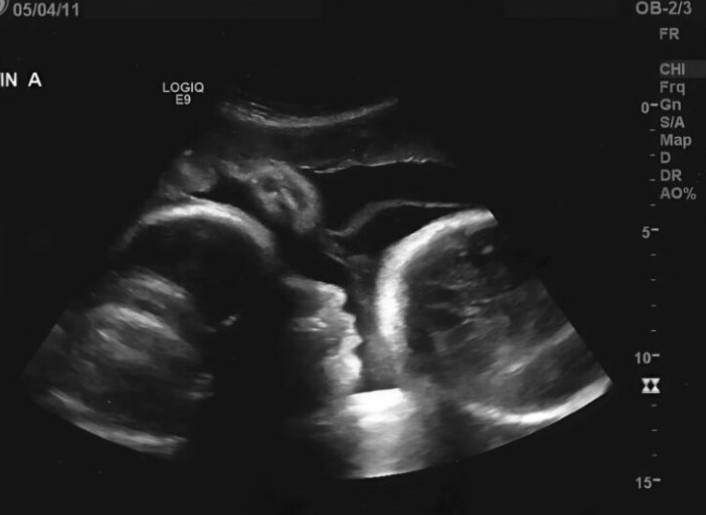

Toen de dokter naar het ultrascherm keek, verbleekte zijn gezicht plotseling. Met een trillende stem vertelde hij de harde waarheid. Larisa was niet zwanger; de eerste tests hadden een misleidend resultaat gegeven. De zwelling in haar buik werd niet veroorzaakt door een groeiende baby, maar door een enorme tumor in haar eierstok die haar lichaam van binnenuit aantastte.

De woorden van de dokter waren verwoestend voor Larisa. Het “gevoel van beweging” in haar buik bleek niets meer te zijn dan de druk van de tumor op haar organen. Bovendien had de ziekte zich al verspreid, omdat ze zo lang had gewacht met het zoeken van medische hulp. De arts zei eerlijk: “Als u eerder was gekomen, hadden we u kunnen redden, maar nu is de situatie zeer kritiek.”